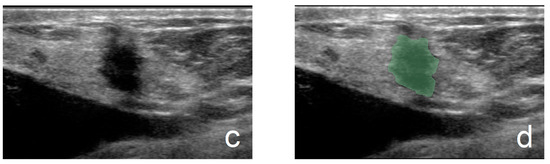

Another junior physician delineated the ROIs for all lesions without prior knowledge of the nodules’ pathological results. ROI delineation was performed using 3D Slicer software (version 5.6.1). All ultrasound images were standardized. During the delineation process, the physician used tools such as zooming, dragging, drawing, and tracing to precisely outline the margins of the lesions. For lesions with unclear margins, the delineations were reviewed and corrected by a senior physician. Figure 1 illustrates the ROI segmentation for benign and malignant breast nodules in ultrasound images. The completed ROI masks were saved in nii.gz format, and the standardized ultrasound images were saved in nii format, preparing them for subsequent ultrasound feature extraction in the Python language environment.

Figure 1.

(a,b) From a 45-year-old patient (fibroadenoma): (a) grayscale image and (b) ROI of a benign breast nodule. (c,d) From a 59-year-old patient (invasive ductal carcinoma): (c) grayscale image and (d) ROI of a malignant breast nodule.